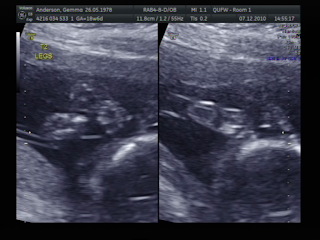

| Janga was sleeping when the scan began (little hands under head). That didn't last long. |

| Jue's little face |

| Jenga ~ He's a BOY!! |

| Jue ~ He's a BOY!! |

| Jue ~ 3D face (didn't stay still long enough to get a good picture) |

| Jue ~ going to sleep after a long scan |

They are both growing well and are a healthy size. They are very active and at the time of the scan where happily kicking each other in the head (one was head up and the other was head down). There are no signs of any problems at the moment but I will need 3 weekly scan to make sure that they are both sharing nicely as TTTTF (Twin To Twin Transfusion) can happen at any time.